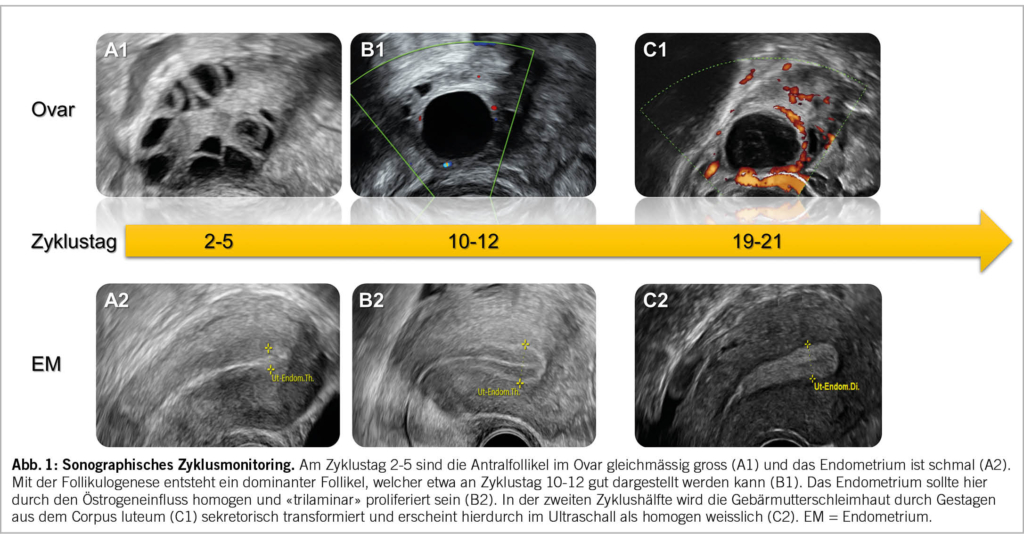

Bei einer Patientin mit Kinderwunsch bzw. Wunsch nach Fertilitätsdiagnostik sollte nach erfolgter Erstkonsultation mit Anamnese und klinischer Untersuchung ein sogenanntes sonographisches Zyklusmonitoring (Abb. 1) durchgeführt werden.

Die Patientin wird gebeten, sich bei Menstruationsbeginn zu melden, um zwischen Zyklustag 2-5 einen Untersuchungstermin zu erhalten. Bei dieser Untersuchung am Zyklusanfang sollten die Antralfollikel im Ovar gleichmässig gross (ca. 2-8 mm) und das Endometrium schmal sein (Abb. 1A1 & Abb. 1A2). Durch das einfache Zählen der vorhandenen Eibläschen in den Ovarien lässt sich der sogenannte «antral follicle count (AFC)» (Abb. 2A) erheben, der nachgewiesenermassen gut mit dem Anti-Müller-Hormon (AMH) korreliert und so eine verlässliche Aussage über die vorhandene Eizellreserve der Patientin zulässt (7). Je nach Alter existieren unterschiedliche Normalwerte für den AFC, die an Perzentilenkurven in der Literatur abgelesen werden können (8). Frauen mit polyzystischem Ovarsyndrom (PCOS) haben in der Regel eine ausserordentlich hohe Eizellreserve, die sich typischerweise in einer polyzystischen Ovarmorphologie (PCOM) manifestiert. Die zahlreichen und verhältnismässig kleinen Antralfollikel können hier in den Ovarien «perlschnurartig» angeordnet sein (Abb. 2B) (9). An dieser Stelle ist es wichtig zu erwähnen, dass die perlschnurartige Anordnung nach den Rotterdam-Kriterien kein sonographisches Diagnosekriterium für das PCOS ist. Massgeblich ist die Anzahl der frühzyklisch bestimmten Antralfollikel (mind. 20 pro Ovar) und/oder des Ovarvolumens (mind. 10 ml) (10).

Die zweite Untersuchung sollte am Zyklustag 10-12 bzw. zur Zyklusmitte hin erfolgen. Durch die Follikulogenese sollte ein dominanter Follikel entstanden sein (Abb. 1B1), welcher je nach Durchmesser (ca. 12-20 mm) eine zeitliche Aussage über die anstehende Ovulation zulässt (der Leitfollikel vergrössert sich im Durchschnitt um etwa 2 mm in zwei Tagen, wobei sein mittlerer Ovulationsdurchmesser bei ca. 22-24 mm liegt). Das Endometrium sollte durch den zunehmenden Östrogeneinfluss homogen «trilaminar» proliferiert sein und keine Unebenheiten aufweisen (Abb. 1B2). Die trilaminare Struktur hat nach aktueller Datenlage einen relevanten Einfluss auf die Fruchtbarkeit einer Frau, während die Endometriumdicke entgegen verbreiteter Annahmen eine eher untergeordnete Rolle spielt (12–15).

Das Zyklusmonitoring kann bei Bedarf durch eine Ultraschalluntersuchung in der Lutealphase ergänzt werden. Diese sollte etwa an Zyklustag 19-21 erfolgen. Ist bei dieser Untersuchung ein Gelbkörper durch den sogenannten «ring of fire» nachweisbar (Abb. 1C1) und die Schleimhaut durch den Gestageneinfluss sekretorisch transformiert bzw. homogen weisslich, so entspricht dies dem sonographischen Normalbefund (Abb. 1C2).